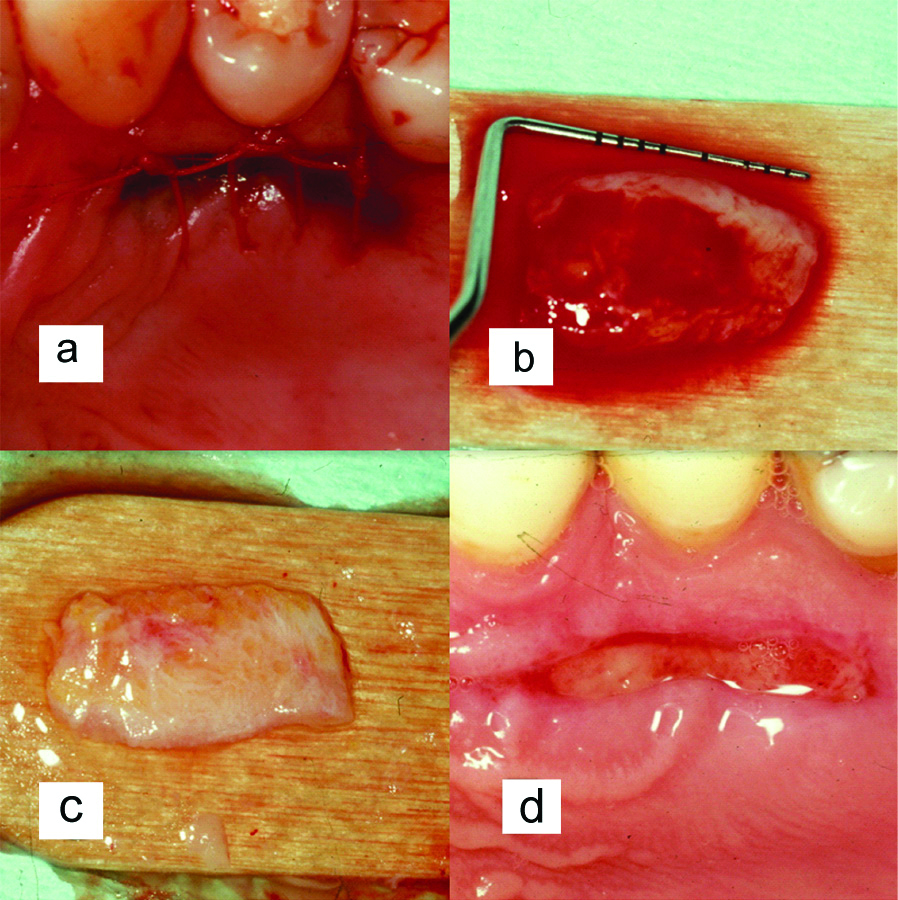

A 36-year-old female patient presented in to the periodontal clinic in 2002 with a complaint of long teeth and sensitivity in the lower right (#43) and left (#33) canines. The dental history revealed that the patient had a history of using an aggressive brushing technique, which caused generalised abrasion of the cervical region and resulted in the placement of a composite restoration to fill the abrasion area. Subsequently, gingival recession occurred in some areas, and root sensitivity reoccurred because of a leakage of these restorations. Clinical examination revealed the presence of gingival recessions of approximately 3-4 mm on teeth #33 and #43, with the presence of a composite restoration on the root surface [Table/Fig-1]. The recession defect was classified as Miller’s Class II, with 1 mm of a keratinised gingiva and no attached gingiva [1]. The probing depth ranged from 1 to 2 mm. The plaque index was 75%, with bleeding on probing of 55%. Phase I therapy consisted of scaling and root planing, with plaque control measures using a modified Stillman’s brushing technique and interdental flossing at home. The surgical phase consisted of removal of the old restoration and replaced with a new restoration which; was contoured to the crown only then, placement of a connective tissue graft, combined with a double-papilla flap. The patient agreed to the procedure and signed informed consent. Prior to soft tissue grafting, the composite restoration was removed from the root surface and contoured to the tooth crown only, and the root surface was smoothed with a finishing bur [Table/Fig-2]. The right side of the palate was used as a donor site, which was anaesthetised with one ampoule of lidocaine, while each recipient site received two ampoules. Blade #15 was used for incision placement and palatal tissue harvesting. Two oblique incisions of 3 mm long were placed on each side of the tooth, with two vertical incisions extended beyond the mucogingival junction. A partial thickness flap was utilised all the way long [Table/Fig-3]. A connective tissue graft of 13×5 mm, with 2-mm thickness after removal of adipose tissue, was harvested from the palate, and the donor site was secured with a 4-0 vicryl suture [Table/Fig-4]. The graft was divided in half, for teeth #33 and #43, respectively. The graft was then, sutured in place with a 5-0 vicryl suture using a simple interrupted technique; then, a double-papilla rotational flap was secured with 5-0 vicryl [Table/Fig-5]. No periodontal dressing was used. Postsurgical medication consisted of ibuprofen 400 mg/qid for four to seven days and rinsing with normal saline twice daily for seven days. The patient was instructed to eat soft food for seven days. Brushing of the surgical site was deferred for six weeks, and the patient was asked to use a cotton tip with mouthwash to clean the area twice daily. The sutures were removed after two weeks, and the healing was uneventful, with no complications [Table/Fig-6]. Since the patient had mild localised periodontitis, with a history of an aggressive brushing technique, she was placed on a maintenance recall every four months for suppurative periodontal therapy.

a) Palatal donor site; b) Approximately 13 mm of tissue harvested; c) Palatal tissue after removal of adipose tissue; d) Donor site after two weeks of healing.